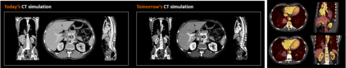

2. 高空間分解能による構造識別の精緻化:0.2mmピクセルの高精細画像を、低線量で取得することが可能です。これにより、標的腫瘍の同定や正常組織との識別精度が向上し、正確な標的体積の設定や正常組織の同定に繋がります。

[画像3]https://digitalpr.jp/simg/2303/123144/650_127_2025112115564169200d29c146e.png